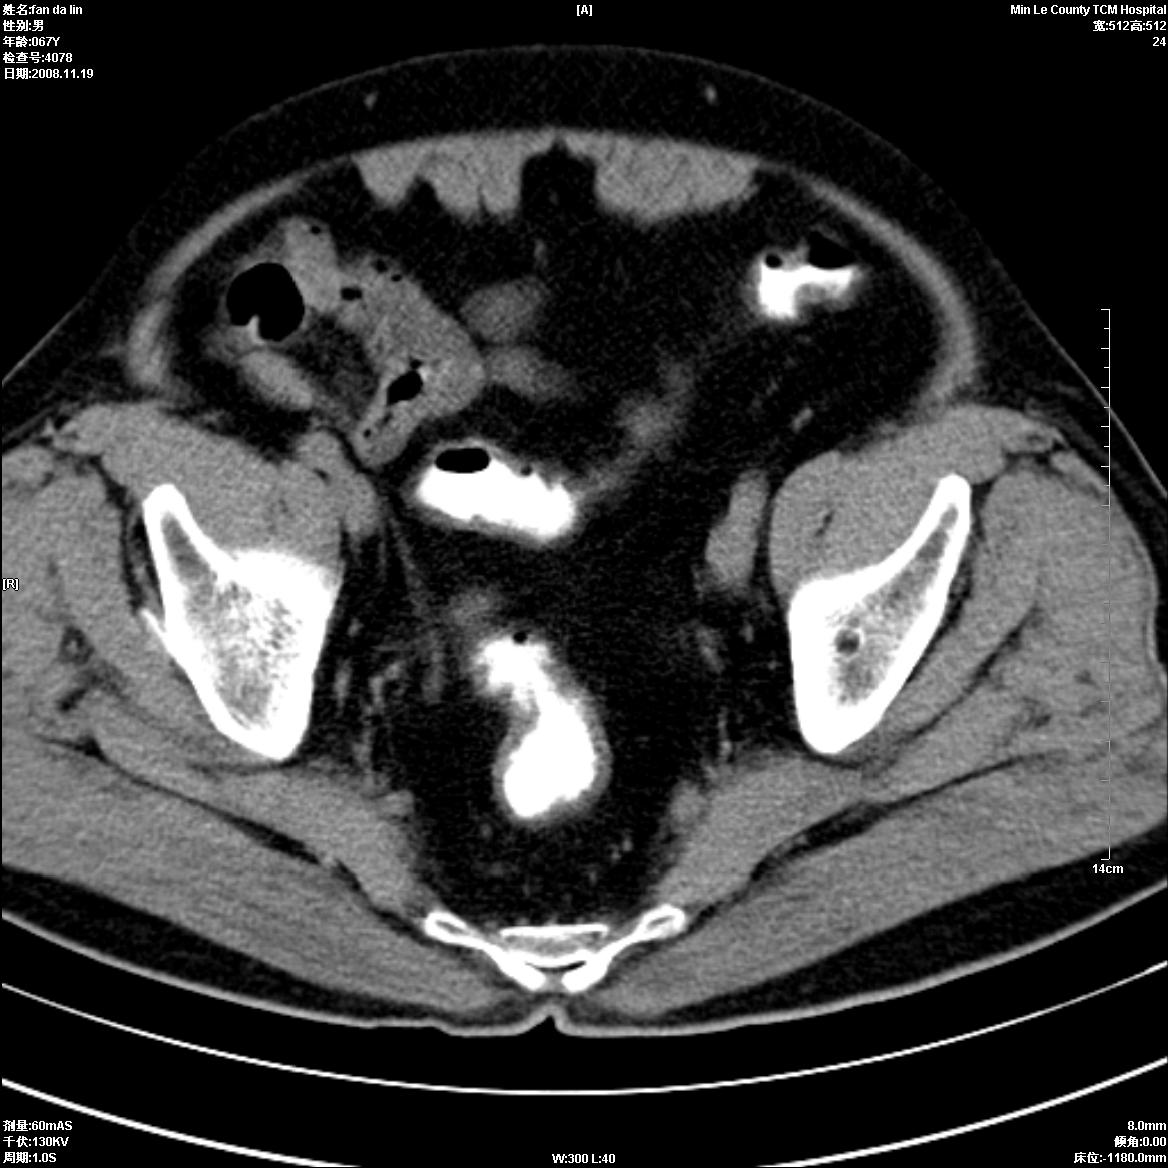

标题: CT16698:M67Y,看看直肠下端是不是病变 [打印本页]

标题: CT16698:M67Y,看看直肠下端是不是病变

直肠及乙状结肠管壁均增厚,考虑炎症.

直乙交界处肠壁不规则增厚,还是做个肠镜吧

只是肠壁局限性增厚,但难说明问题。